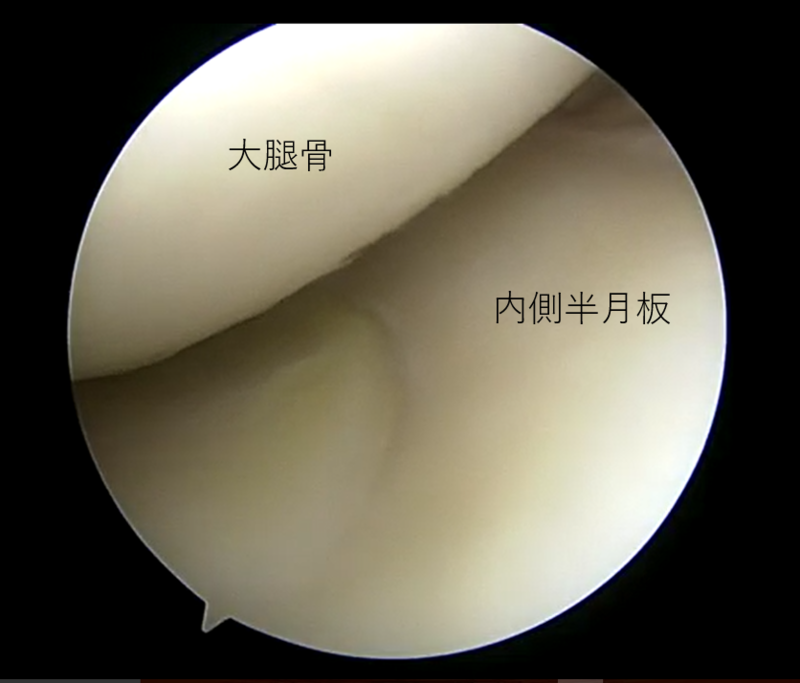

| 内側半月板問題なし | 外側半月板フラップ損傷 | 大腿骨側の軟骨損傷部 |